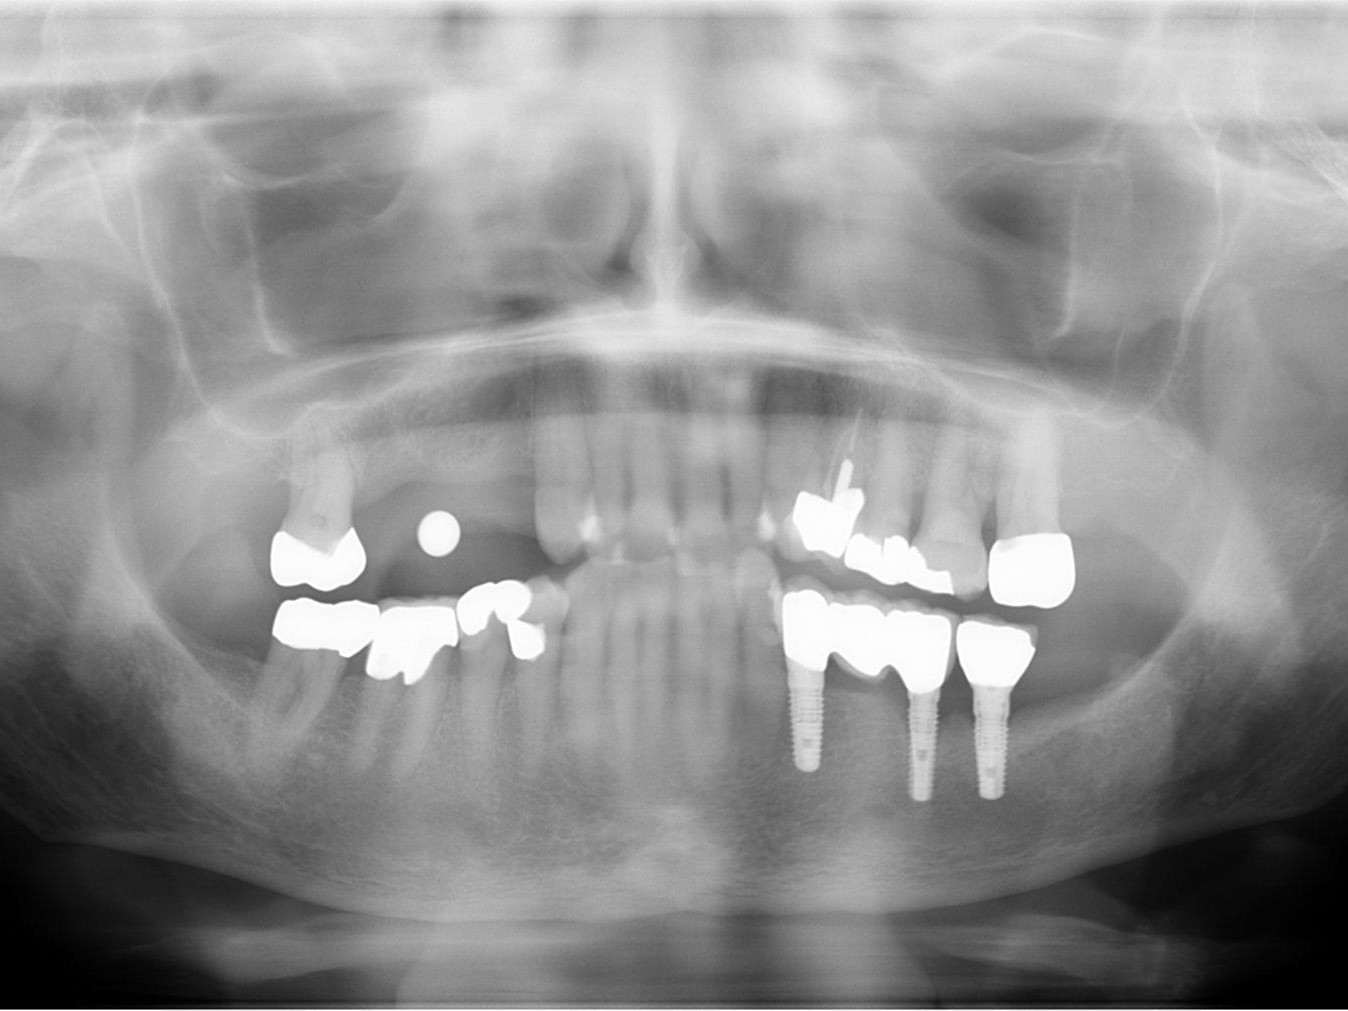

Abb. 1: Ausgangsituation Zahnfilm

Die 76-jährige Patientin stellt sich mit einer seit Jahren bestehenden Brückenversorgung im ersten Quadranten in der Praxis vor (Abb. 1). Die Pfeilerzähne 14 und 16 waren seit Jahren wurzelkanalbehandelt. Der mesiale Brückenpfeilerzahn zeigte eine apikale Beherdung mit Parodontalspaltverbreiterung. Insgesamt wies die Brücke einen Lockerungsgrad von 1 bis 2 auf. Die hauszahnärztlich angebotene erneute zahngetragene Brückenversorgung mit Ausdehnung auf den Eckzahn 13 wurde von der Patientin nicht favorisiert. Deshalb wurde der Patientin eine Entfernung der gesamten Brücke mit Sofortimplantation und Sofortversorgung in Nonokklusion angeraten (Abb. 2). Es wurden in Lokalanästhesie drei Straumann Bone Level Tapered Implantate gesetzt. In derselben Sitzung erfolgte die konventionelle Abformung beider Kiefer. Binnen 24 Stunden wurde ein verschraubtes und verblocktes Langzeitprovisorium aus PMMA auf Klebebasen (Straumann) in Nonokklusion erstellt (Abb. 3). Dieses Langzeitprovisorium verblieb 26 Monate in situ. Nach dem Entfernen des Langzeitprovisoriums zeigten sich perfekt ausgeformte Schleimhautemergenzprofile. Es wurden die entsprechenden Scanbodys eingeschraubt. Die Scandaten wurde mit dem 3Shape Trios 3 von Straumann erhoben und dem Labor übersandt (Abb. 4). Die Farbbestimmung erfolgte über den Scanner.

Abb. 20: Abschluß-OPG